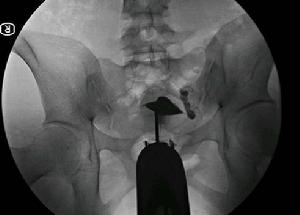

輸卵管導絲擴張疏通術治療步驟

輸卵管鏡、宮腔鏡技術引導檢查

將手術導管通過宮頸放至子宮的開口部位,管中不足毫米的超軟頭納米導絲,在宮腹腔鏡(或X射線)和輸卵管鏡的引導下,通過輸卵管探查、造影、通液等方式,詳細檢查輸卵管病變部位。

納米導絲推進疏通

利用納米導絲的推進、擴張、分離作用和造影劑所產生的衝擊力,快速、安全、有效的使輸卵管疏通至其傘端部位,解決輸卵管的粘連、堵塞問題。

術中同時置藥防復發

在疏通輸卵管的同時,通過導絲在病變部位部位準確置入預防粘連的藥物,使其在藥物的作用恢復自然形態與正常功能,從而徹底治癒輸卵管性不孕,防止疾病復發。